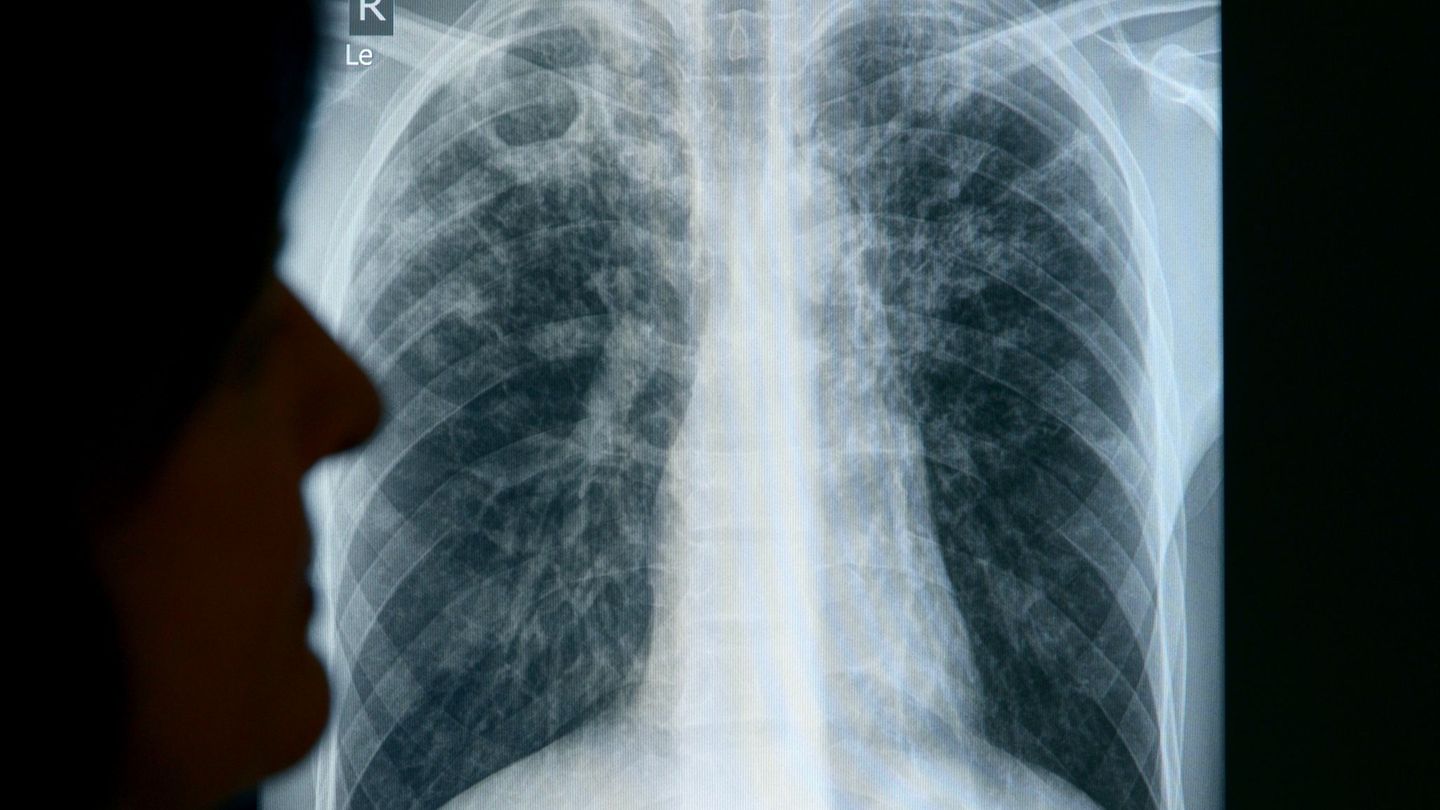

Es wurde ein weiterer Tuberkulose-Fall im Landkreis Bautzen festgestellt. (Symbolbild) Foto: Rainer Jensen/dpa

Tuberkulose ist eine Infektionskrankheit, die durch Bakterien verursacht wird und überwiegend die Lunge betrifft. Sie wird übertragen, wenn infizierte Menschen beim Husten und Niesen Erreger ausscheiden. Ohne Behandlung stirbt nach Angaben der Weltgesundheitsorganisation etwa die Hälfte der Infizierten. Mit einer vier- bis sechsmonatigen Behandlung können rund 85 Prozent der Menschen geheilt werden.